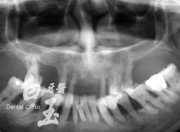

患者全口 X 光

治療前